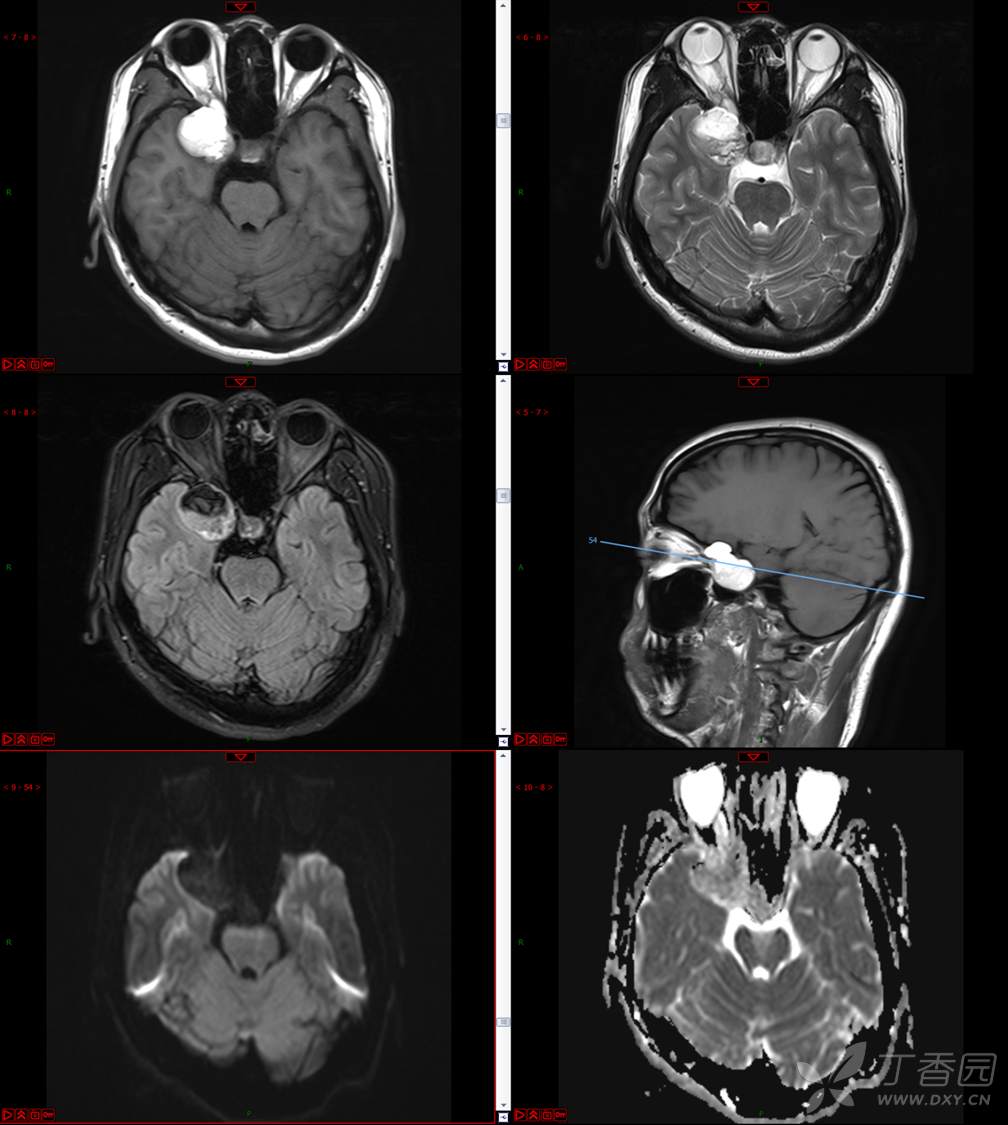

【影诊笔记534】青年男性,视物模糊就诊,CT、MRI、MRS齐全,请分析~~~

主 诉:视物重影5天。

现病史:患者5天前无明显诱因出现视物重影,表现为右视时视物成双,无头痛、头晕,无恶心、呕吐,无面部麻木、饮水呛咳等,于当地医院就诊,行颅脑MR示“颅内占位性病变”,现为求进一步治疗来诊。患者病来精神可,饮食、睡眠正常,体重无明显变化。